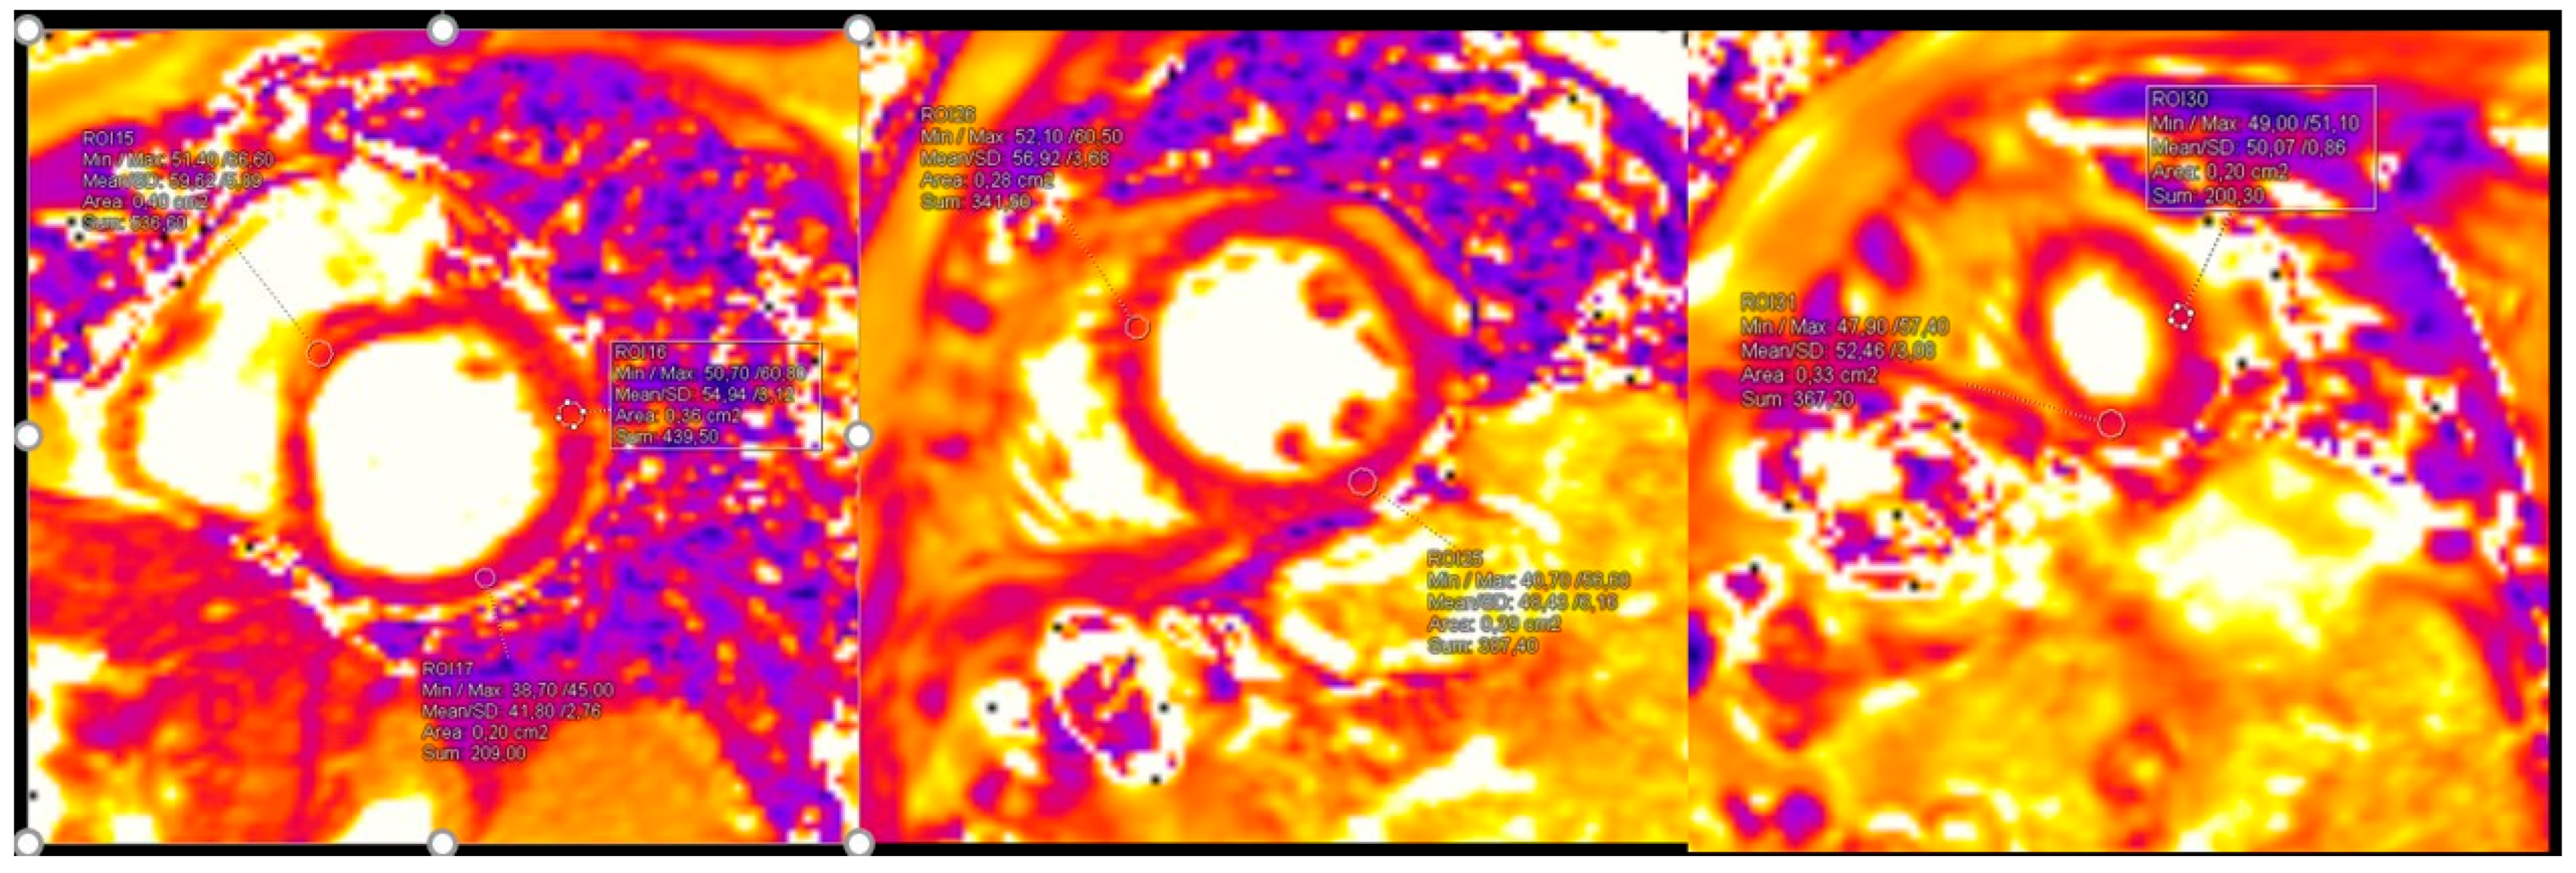

| T1 native, ms (mean ± SD) | 1035.94 ± 111.43 |

| T1 native increase, n (%) | 14 (21.0) |

| T1 post-contrast, ms (mean ± SD) | 440.81 ± 99.55 |

| T1 post-contrast increase, n (%) | 13 (19.4) |

| T2 native, ms (mean ± SD) | 45.21 ± 3.05 |

| T2 post-contrast increase, n (%) | 15 (22.4) |

| LGE positive, n (%) | 29 (43.3) |

| LGE in ≥3 segments, n (%) | 25 (37.3) |

| LGE layers, n (%) | |

| epi | 11 (37.9) |

| epi or mid | 12 (41.4) |

| mid | 6 (20.7) |

| Total abnormal, n (%) | 39 (58.2) |

| LGE positive in T1 native increase patients (%) | 50.0 |

| LGE positive in T1 post-contrast increase patients (%) | 30.8 |

| LGE positive in T2 native increase patients (%) | 70.0 |

| Pericarditis, n (%) | 8 (12.5) |